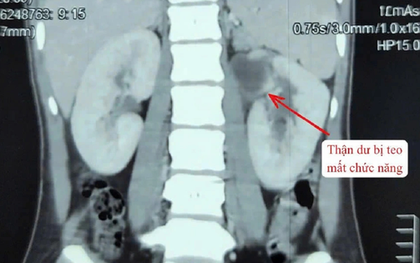

Kỳ lạ cô gái 22 tuổi có 3 quả thận

Một phụ nữ 22 tuổi ở Đà Nẵng được bác sĩ phát hiện dị tật bẩm sinh hiếm. Theo các bác sĩ, những trường hợp có 3 quả thận chỉ chiếm 1% dân số. Bệnh có thể gây nhiễm trùng tiết niệu tái phát, tiểu buốt, tiểu rắt, đau vùng hông lưng.